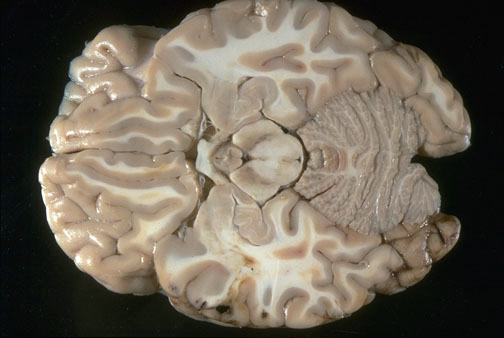

Identify the following regions of the brain on transverse section by clicking in the image below:

Optic Chiasm - Mammillary Bodies - Midbrain - Gyrus Ructus - Cerebellum - Amygdala - Hippocampus - Orbital Gyrus - Infundibulum